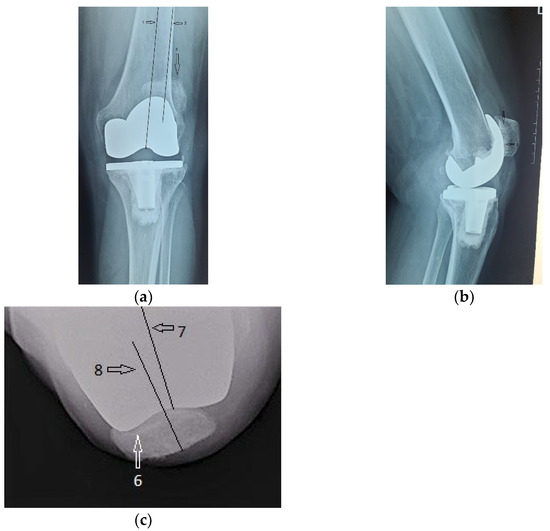

Radiological and clinical follow-up were performed at 6 weeks, 3 months and then 12 months after surgery (Figure 7, Figure 8 and Figure 9).

Figure 8.

Radiological imaging at 3 months after surgery. (a) Coronal view, patella is centered to the femoral component (arrow); (b) lateral view.

Figure 9.

12 months after surgery: (a) coronal view, normal centered patella; (b) lateral view, no signs of patellar loosening; (c) axial view, normal centered patella in femoral trochlea.

The clinical evolution of the patient was also satisfactory. The anterior knee pain decreased significantly at 6 weeks after surgery and was absent at 3 months. At the same time, we recorded a significant improvement of the joint function, the episodes of swelling being completely absent. The aspect at 12 months after surgery is shown in Figure 10. The patient can easily achieve 120 degrees flexion without pain, full extension without joint swelling and is able at climbing stairs and get up from a chair, without pain.